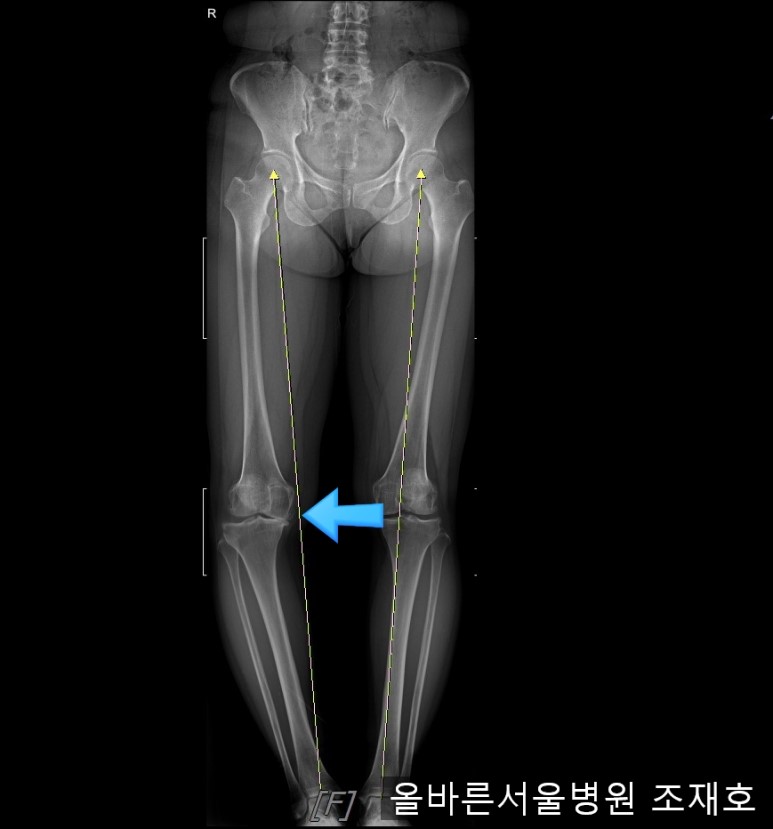

某患者,女,54岁,大面积软骨损伤,伴随内翻畸形,实施非切开CARTSTIEM手术及胫骨近端外翻截骨术,2、3年前右侧膝盖开始疼痛,在其他医院做了两次关节镜手术后疼痛加剧,膝关节变形严重遂到本院接受治疗。

仅通过放射线片子观察到:右膝由于炎症严重,内侧胫骨及股骨已接触在一起,向内测严重变形。

观察膝盖下肢排列的扫描图像可看到右腿严重变形,身体中心向内倾斜。